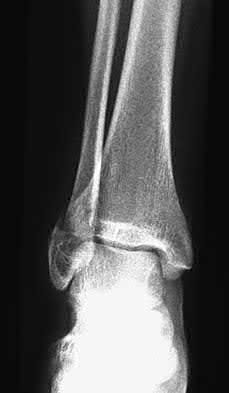

A 25-year-old female is involved in a motor vehicle collision. She presents with the isolated injury seen in Figures A through D. Her leg is swollen but her skin is intact. She has no clinical signs of compartment syndrome. Which of the following treatment options will allow for maintenance of fracture alignment and minimize the risk of soft tissue complications?

The patient presents with a closed distal third metaphyseal-diaphyseal distal tibia fracture with simple intra-articular extension. Immediate intramedullary nailing along with percutaneous fixation of the articular component provides appropriate restoration of length, rotation and alignment and minimizes the risk of wound complication.

Displaced distal third tibia fractures may be associated with simple intraarticular extension. Operative treatment of intra-articular distal tibia fractures has historically been performed with open reduction and internal fixation. Early open reduction and plate fixation of pilon fractures has been associated with high rates of infection and wound complication. In select patterns with simple articular extension, percutaneous screw fixation and medullary nailing may provide appropriate reduction with minimal soft-tissue risk.

Figures A and B demonstrate a distal third tibial shaft fracture with simple intra-articular extension. The axial and coronal CT cuts in Figures C and D further clarify the articular injury. Illustrations A and B demonstrate a comminuted distal third tibial fracture with simple intra-articular extension. Illustrations C and D are fluoroscopic images of the same injury after intramedullary nailing and percutaneous fixation of the articular component.